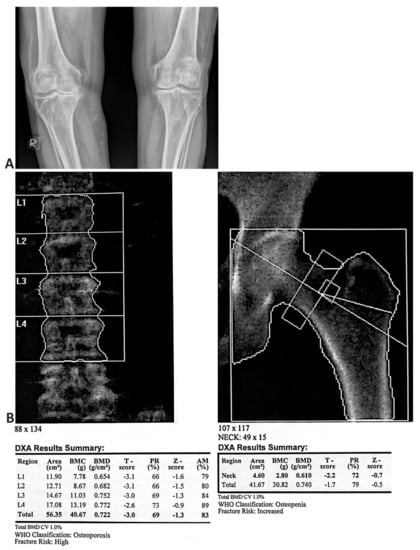

The radiological findings of the knee in PA projection and the DXA findings of the spine and hip in the same patient with OA and OP are presented in Figure 3. Osteoarthritis of a significant degree is shown on the right knee: asymmetric narrowing of the joint fissure, beaked circular osteophytes, and spinous processes on the intercondylar eminence. A poorly defined zone of demineralisation is shown under the lateral tibial plateau. A similar morphology finding is significantly more discrete for the left knee.

Figure 3. (A) posteroanterior radiographic view of bilateral knees demonstrating advanced osteoarthritis. (B) the bone density scan (DXA) of a 63-year-old postmenopausal woman with advanced knee osteoarthritis (OA) showing osteoporosis (BMD) of the spine and osteopenia of the hip.